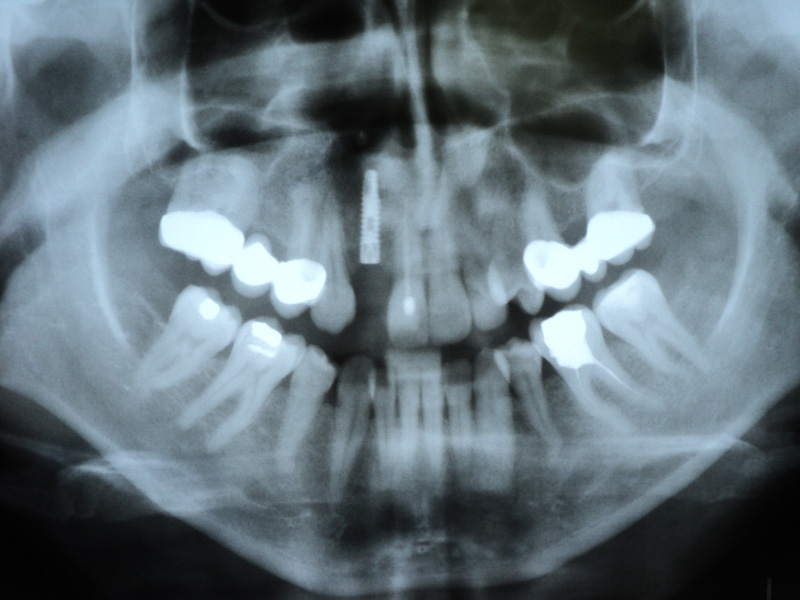

Implante - Galerie Foto

Caz II